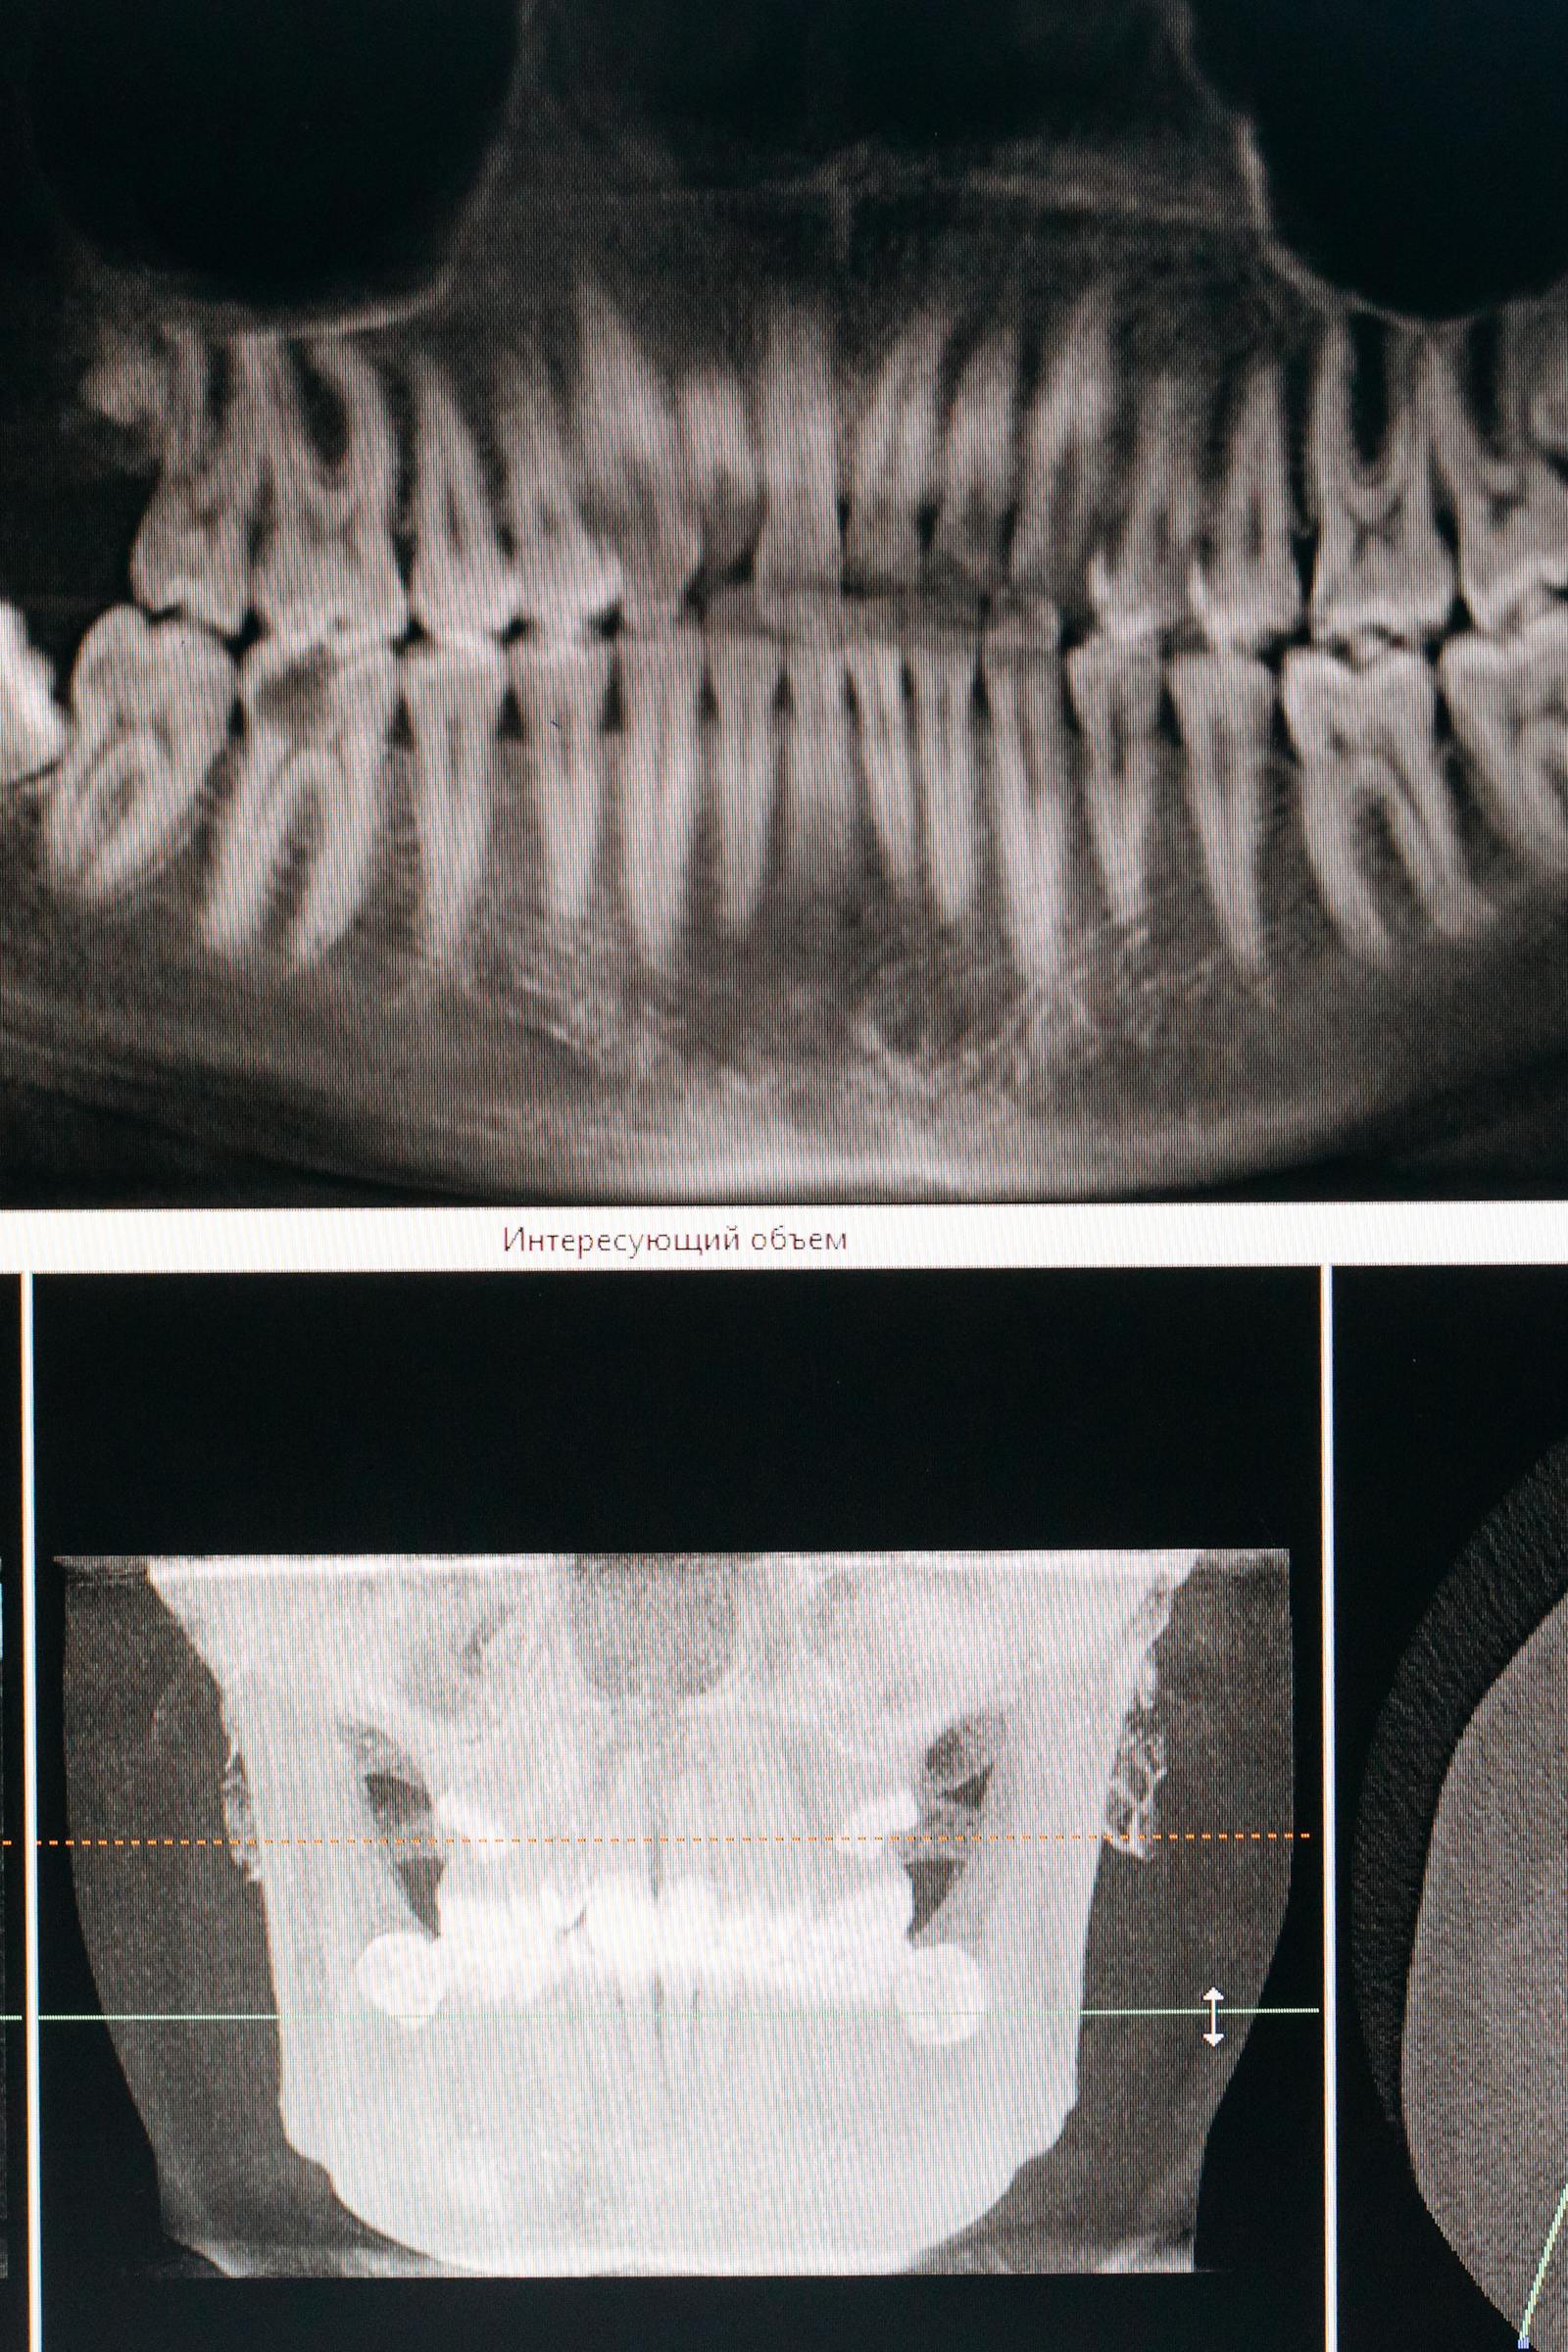

General Dentistry

Healthy smiles start with strong foundations. At Mississauga Hanin Dental, we offer routine cleanings, exams, fillings, and gum care to keep your teeth in top shape. We focus on prevention, early treatment, and personalized care for lasting oral health.

Root Canal Treatment

Wisdom Tooth Extractions